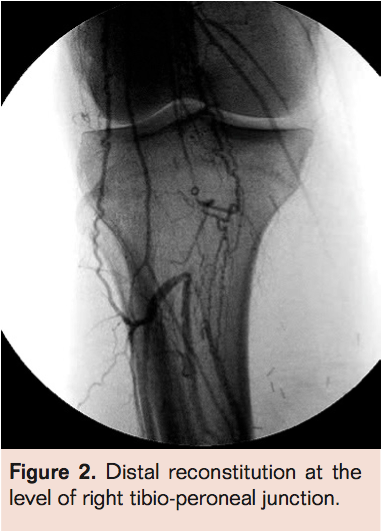

- Cross occlusion with guidewire of choice (must exchange for .014 guidewire if larger wires used to cross) (Figure 2)

- Laser thrombectomy with a 0.9 mm probe advanced 1 mm/sec with saline flush via the sheath (Figure 3)